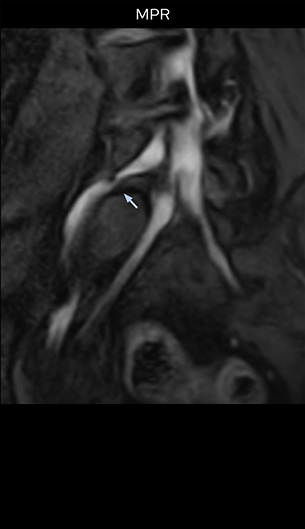

“For example, in sagittal images, when the presence of fat is observed in the intervertebral foramen, it suggests that there is a margin around the nerve. Similarly, the absence of fat indicates that the nerve is being compressed. So, we used to deduce nerve compression indirectly. With NerveVIEW, however, we can observe the condition of the nerves directly, regardless of the presence or absence of fat. We always prefer such direct observation of anatomy over having to make an inference about it.”

“Although symptoms of typical disc herniation and atypical hernia are very similar, the actual site of herniation is different. It is therefore important to characterize the nerve’s condition both inside and outside of the intervertebral foramina. “Conversely, if we see no abnormality in NerveVIEW, we can assume at least that there is no severe condition that requires surgery. Like this, it can help us avoid unnecessary surgery. NerveVIEW can have a tremendous impact in this way.”

“The intra-luminal signal of veins, especially around the intervertebral space, can be suppressed well with NerveVIEW. As a result, we can easily observe the detailed nerve structure around the posterior ganglion,” he says. “This is why we use 3D NerveVIEW for intraforaminal stenosis and extraforaminal stenosis/herniation (lateral disc herniation). On the other hand, if herniation is suspected to exist inside the dorsal root ganglion (DRG), balanced TFE or ProSet-FFE is applied. NerveVIEW is not suitable for evaluating the median type of herniation.” The SE-EPI DWI-based method for MR neurography works well for large FOV exams like whole-body MRI, but focal examination of nerves is often limited by the attainable spatial resolution (both inplane and slice direction) and geometric distortion. “3D NerveVIEW achieves higher in-plane resolution – close to our other routine spine sequences – and the source images can be used instead of adding a fat-suppressed T2-weighted sequence,” Tanji says.